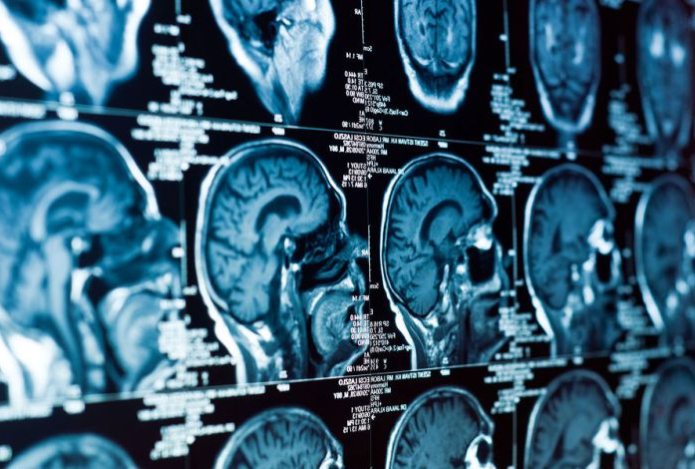

Стресс может нарушать мозговое кровообращение

Ученые из Пенсильванского университета выяснили, что стресс способен вызывать нарушения кровотока в мозге. Этот фактор способствует развитию болезни Альцгеймера, передает Sports.kz со ссылкой на Gazeta.ru.

Ученые установиои, что у мышей за поддержание нормального кровотока и согласованную активность нейронов отвечают редкие нервные клетки — нейроны nNOS первого типа. Они составляют менее 1% от всех нейронов мозга. Эти клетки крайне чувствительны к стрессу и могут погибать при сильных эмоциональных перегрузках.

Чтобы изучить влияние клеток nNOS, ученые использовали токсин сапорин, избирательно уничтожавший только этот тип нейронов. После воздействия они наблюдали значительное ослабление спонтанных колебаний сосудов мозга и снижение активности нейронов.

Удаление этих нейронов у животных также приводило к снижению как кровотока, так и электрической активности мозга, особенно во время сна. Это, по словам ученых, доказывает, что nNOS-клетки играют ключевую роль в снабжении мозга кислородом и поддержании нейронных связей.

«Снижение кровотока — один из факторов, ускоряющих ухудшение работы мозга и развитие нейродегенеративных заболеваний у людей. Потеря этих редких нейронов из-за хронического стресса может быть недооцененной причиной такого ухудшения», — отметил ведущий автор исследования, профессор инженерных наук Патрик Дрю.

Исследователи считают, что клетки с аналогичными функциями также присутствуют в мозге человека. Понимание их роли может помочь разработать новые способы профилактики возрастных нарушений мозга и, возможно, замедлить развитие деменции.